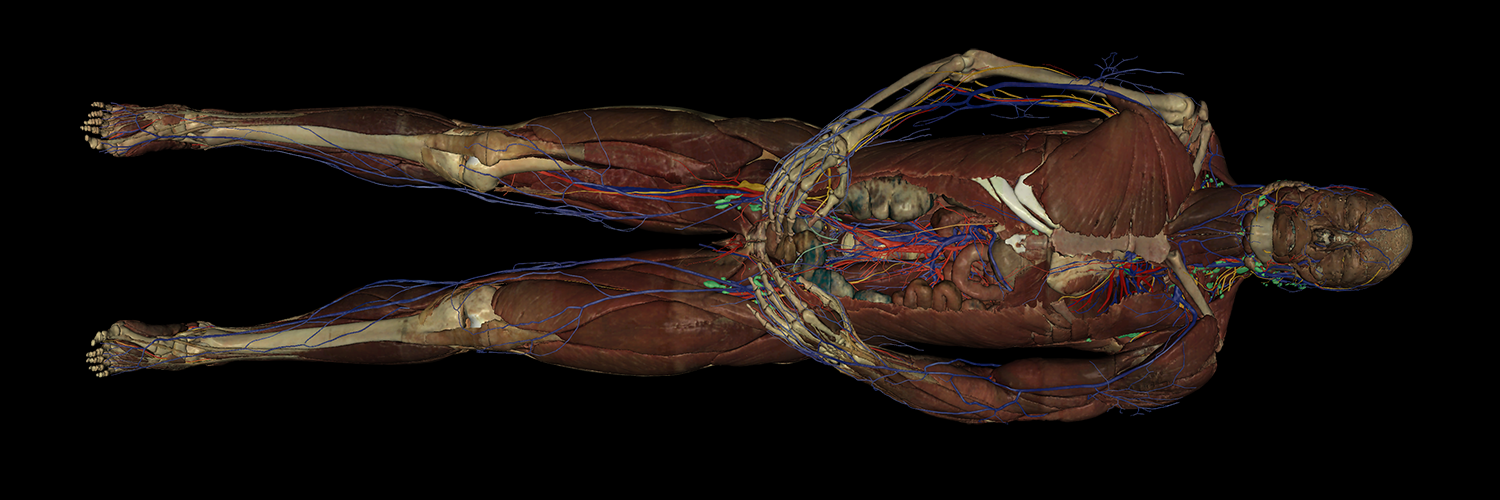

Our #VHDissector’s true color labeled cross-sectional images are an integral part in @BUAnatNeuro's anatomy lab and lectures for MD and PA students. Exposure to anatomical structures and spatial relationships in the cross-sections helps better prepare learners for their careers!